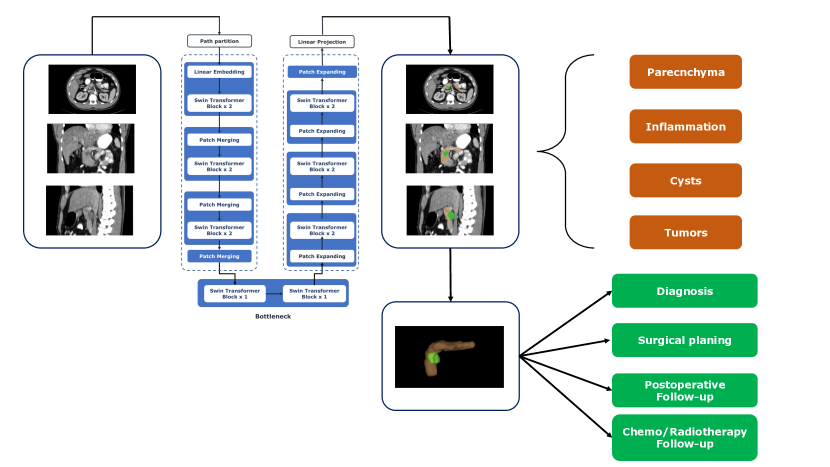

Progress in the past decade in deep learning (DL) has led to continuous improvements in medical imaging, including pancreas segmentation. An overview of pancreas segmentation based on DL is depicted in 1. Even though in the last years several reviews have delved into pancreas segmentation from CT scans using AI (Ghorpade et al., 2023; Kumar et al., 2019; Huang et al., 2022a; Yao et al., 2019; Aljabri and AlGhamdi, 2022; Rehman and Khan, 2020; Senkyire and Liu, 2021), our preliminary literature search has unearthed a significant number of studies overlooked by them. These considerations underscore the necessity for an updated systematic review to comprehensively cover the latest advancements in the field. Consequently, the goal of this review is to present systematically an in-depth analysis of DL for the segmentation of the parenchyma, tumors, cysts, and inflammation of the pancreas starting from CT scans.

Given the rising demand for enhanced early detection of pancreatic diseases, precise segmentation from medical images has become imperative. In this regard, its segmentation from medical images is a prerequisite for accurate computer-assisted diagnosis, surgical navigation, post-surgical follow-up, and radiotherapy.